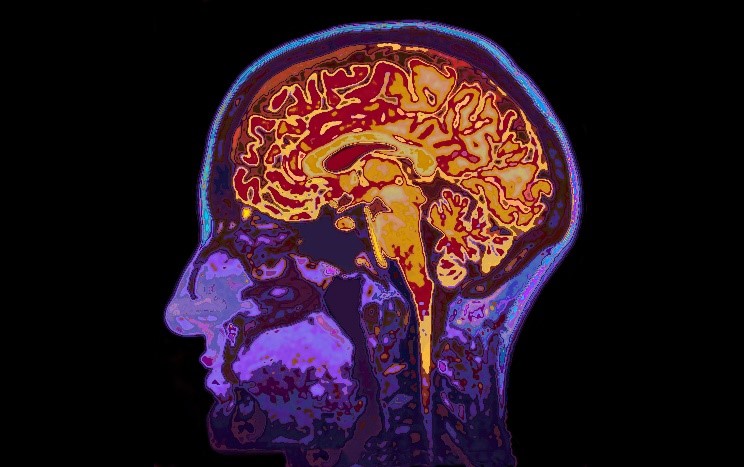

3 Things to Help You Prepare for an MRI Brain Scan

MRI brain scans can detect many issues in the brain, such as cysts, tumors, bleeding, swelling, inflammatory conditions, and other abnormalities. During an MRI brain scan, you are required to sit or lay still for an extended period of time. If you have a fear of tight spaces, ImageCare offers you medication to take before your scan to help you feel more comfortable. Aside from this sedation MRI, ImageCare also offers an open MRI machine which provides much more room. Our Hitachi Oasis High Field open MRI decreases the feeling of claustrophobia in patients without sacrificing the diagnostic accuracy of images taken. We also offer a Stand Up MRI that allows patients to watch television during the exam.